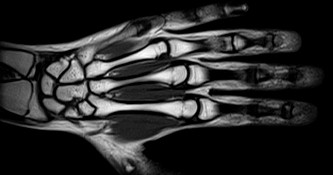

МРТ 1.5 Лучезапястного сустава

МРТ лучезапястного сустава - это обследование c помощью магнитного поля, без лучевой нагрузки, позволяющее получить изображение костей, связок, мягких тканей сустава.